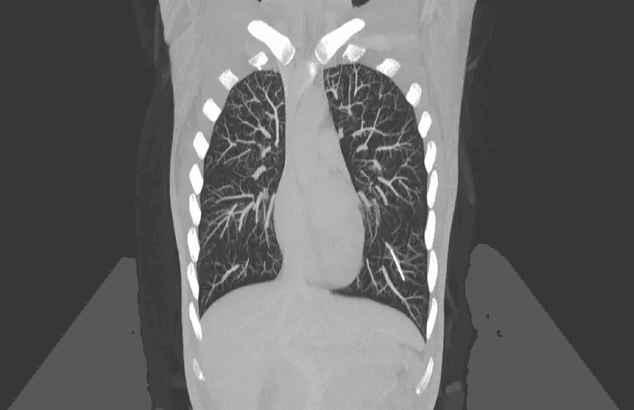

Después de analizar con ella su historial médico y realizar una serie de pruebas de diagnóstico por imagen, los médicos descubrieron que no podía sentir el implante porque el procedimiento original no se había realizado correctamente. Como tal, el implante se desprendió alrededor de una semana después de su inserción y luego se desplazó del tejido debajo de la piel a una vena en la parte superior del brazo de la mujer. Desde allí, llegó al corazón, antes de ser transportado a través de una arteria hasta la parte inferior del pulmón izquierdo, donde finalmente se reveló en exploraciones médicas. Los médicos describieron el caso en un informe publicado el 30 de enero en la revista BMJ Case Reports.

En casos muy raros, los implantes Nexplanon pueden migrar desde la parte superior del brazo a otras partes del cuerpo, como el hombro, la pared torácica o las arterias de los pulmones. Un estudio publicado en 2017 descubrió que se habían notificado 38 casos de migración de implantes a la Administración de Alimentos y Medicamentos de los EE. UU. entre 2006 y 2015. Para ponerlo en contexto, un informe de los Centros para el Control y la Prevención de Enfermedades de 2023 descubrió que aproximadamente 1 de cada 4 mujeres de entre 15 y 49 años en los EE. UU. informaron haber usado alguna vez implantes anticonceptivos o dispositivos intrauterinos.

Otros factores de riesgo para la migración del implante incluyen insertar el implante demasiado profundamente en el tejido del brazo o en una paciente con brazos muy delgados. Si un implante llega a los pulmones, puede causar varios síntomas, como tos (que puede ser sanguinolenta), dificultad para respirar o dolor en el pecho. Si el implante errante sigue activo, las pacientes pueden necesitar cirugía para evitar posibles efectos secundarios, como infertilidad y problemas menstruales, señalaron los autores del informe de caso.

En este caso, la mujer no había experimentado ninguno de estos síntomas. Los médicos también observaron que el implante errante no se había movido después de una consulta de seguimiento seis meses después. Como el implante ya no liberaba progestina, la mujer optó por no someterse a una cirugía para extraerlo.